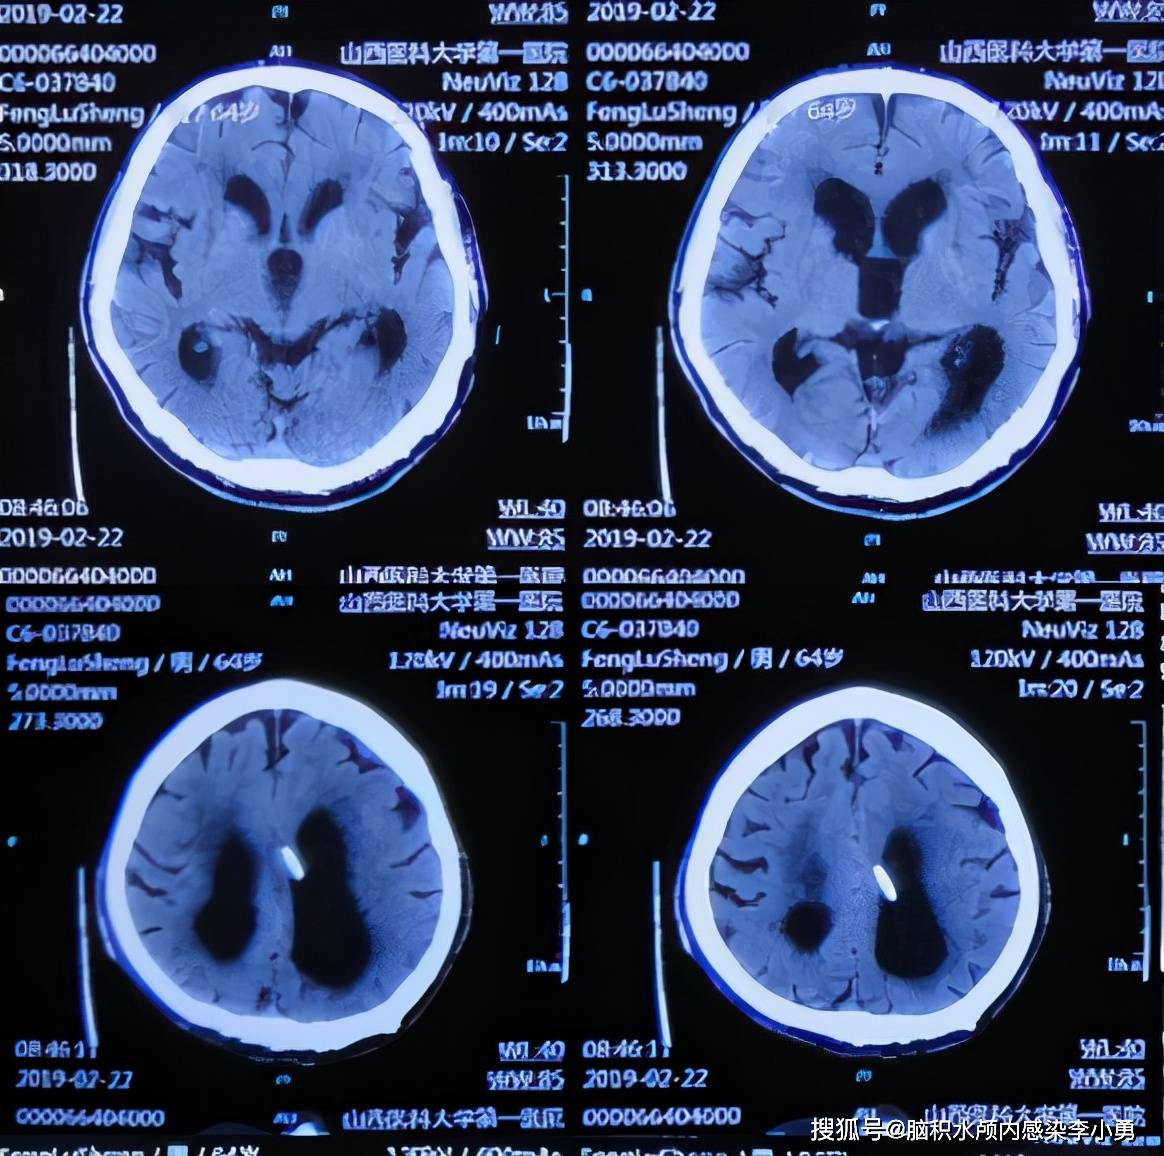

正常大脑和萎缩的大脑,ct和mri检查图像

干货:如何准确鉴别脑积水与脑萎缩?